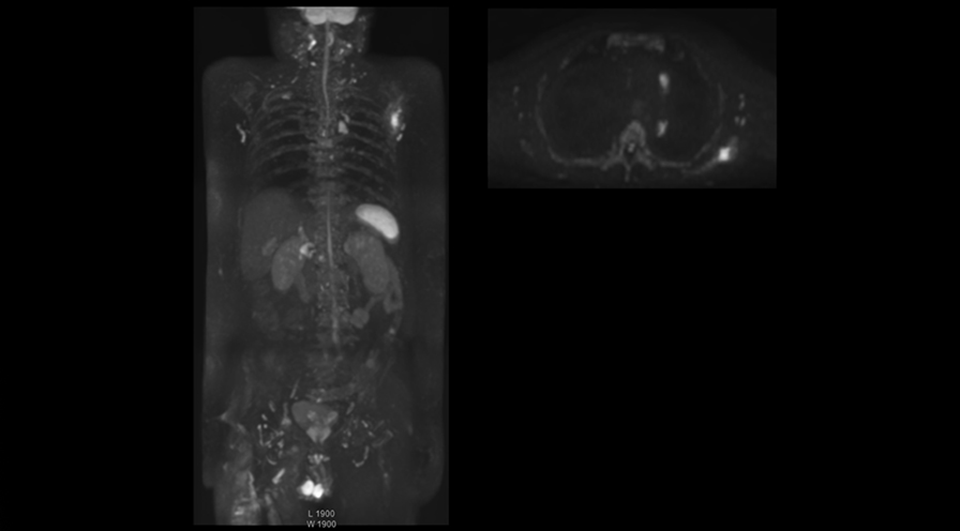

High contrast between lesions and background is beneficial in oncology patients

Radiologist Hiroshi Nobusawa, MD, PhD, explains that the coronal DWIBS protocol for whole body DWI is excellent for visualizing lesions in oncology patients. “About 90% of the DWIBS exams are done in this type of patients. The remainder of DWIBS exams are performed to gain information in cases of fevers of unknown origin,” he says.

“The DWIBS sequence’s value in oncology cases is due to the high contrast it creates between lesions and surrounding tissue. Whole body DWI is requested by physicians who need to clarify TNM staging or determine therapeutic strategies, oncologists in need of diagnosis or follow-up scans, surgeons who need to see the presence of distant lesions that are sometimes difficult to detect by CT before surgery, and urologists for the evaluation of bone lesions, and the effect of chemotherapy and radiotherapy.”

Kawasaki Sawai Hospital’s whole body protocol also includes an mDIXON FFE sequence. Because mDIXON provides images for four contrast types – water only, fat only, in-phase and out-of-phase – from a single acquisition, it is useful in many ways.

“mDIXON FFE allows us to quickly get information we need to assess the presence of fat. That gives us more information when we need to diagnose bone lesions, and when we are asked to judge fat-containing lesions such as hepatocellular or renal carcinoma,” Dr. Nobusawa says.

“The mDIXON fat images can help us to differentiate fatty bone marrow from bone lesions. This is especially useful in elderly people, who tend to have fattier bone marrow. The water images provide a high signal-to-noise ratio in the intestinal canal, which is valuable for visualizing lesions in the colon,” he says.